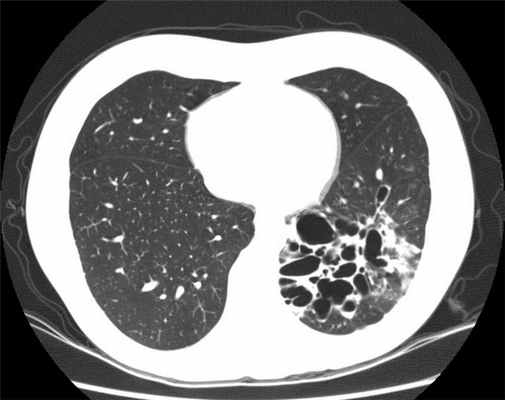

В окончательной постановке диагноза важнейшее значение имеют лучевые методы диагностики. При рентгенографии выявляются тяжистость, ячеистость, кистовидные изменения лёгочного рисунка, уменьшение объёмов отдельных зон лёгкого, эмфизематозность (воздушность) в смежных участках лёгкого. В настоящее время основным диагностическим исследованием является компьютерная томография (КТ, МСКТ). Это связано с большой информативностью метода при неинвазивном и безопасном характере его применения.

- КТ (компьютерная томография): это исследование необходимо для диагностики бронхоэктазов. При этом ваше тело подвергается рентгеновскому облучению под разными углами с последующим компьютерным составлением изображения с высокой точностью.

Достоверный диагноз бронхоэктатической болезни или бронхоэктазов ставится только после проведения компьютерной томографии органов грудной клетки в режиме высокого разрешения

Поставить точный диагноз помогает компьютерная томография с высоким разрешением. Обычная флюорография нужной информации о характере, локализации и развитии БЭБ не даст. Кроме этого специалисты используют другие аппаратные и лабораторные методы, дающие подробные сведения о течении заболевания. Это: